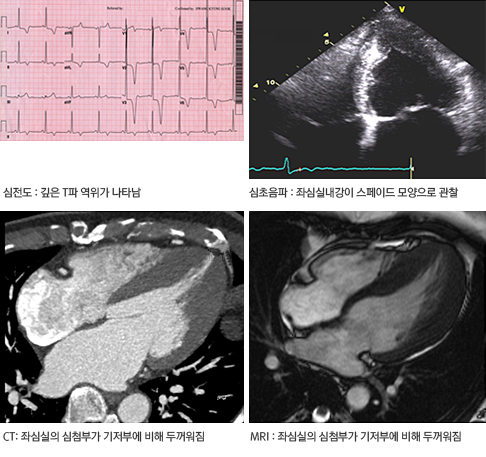

신체검사에서 좌심실 유출로의 폐색이 동반된 환자에서는 심첨 박동이 2개 또는 3개로 나타나는 것이 특징적이며, 이는 심실 수축과 항진된 심방 수축 그리고 이완 초기의 좌심실 충만에 의해 나타난다. 신체검사에서 심잡음이 청진되는 경우가 흔한데, 좌심실 유출로의 폐색이 동반된 환자에서는 수축기 잡음이 흉골좌연을 따라 청진된다. 또 그 소리 크기가 환자의 자세, 발살바법, 운동 등에 따라 다양하게 변화되는 것이 특징이다. 심첨부에서 범수축기잡음이 청진될 수도 있는데 이는 동반된 승모판 역류증에 의한 것이다. 좌심실 유출로 폐색이 있는 환자에서는 경동맥파가 두 개로 관찰된다. 그러나 좌심실 유출로 폐색이 없는 환자에서는 이런 특징적 신체검사 소견이 거의 동반되지 않는다. 95%의 환자에서 심전도 이상 소견을 보이고, 증상이 없는 가족에서도 심전도 이상이 흔히 관찰된다. 좌심실 비대, ST-T 변화, 좌심방 확장, 깊고 얇은 Q파, 외측유도에서 R파의 감소 등이 대표적이다. 하지만 어떤 심전도 소견도 향후 심혈관계 사건을 예측하는 데는 유용하지 못하다. 비후성 심근증의 진단에 가장 유용한 검사는 심초음파 검사로 특징적인 비대칭적 심실중격 비후나 심첨부 비후가 관찰되고 승모판막의 수축기 전방 이동과 그로 인한 좌심실 유출로의 폐색, 승모판 역류증과 같은 다양한 소견을 관찰할 수 있다. 또한 환자의 심부전 증상을 유발하는 좌심실의 이완 기능을 평가하는 데 있어서도 심초음파는 매우 유용하다. 최근 심장 자기공명영상(MRI), 심장 컴퓨터 단층촬영(CT)의 발전으로 비후성 심근증의 진단에 있어 도움이 된다.

심첨부 비후성 심근증 검사